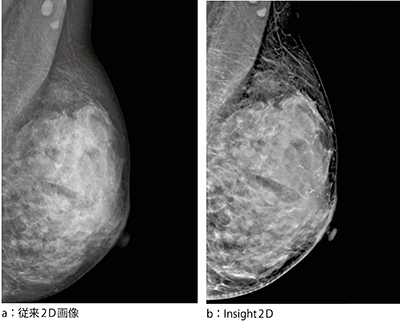

・“Insight2D”:トモシンセシスのスライス画像を構成するための,25枚の収集画像を用いて形成された合成2Dである(図1)。このInsight2Dは,診断価値のあるトモシンセシス画像とセットで読影することにより,将来的に従来の2D撮影に取って代わる技術になると期待されている。

図1 従来2D画像とInsight2Dの比較